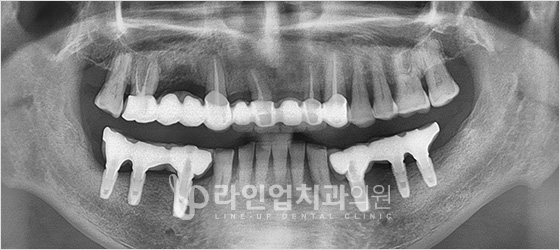

Before

After

Үүдэн шүдний имплант